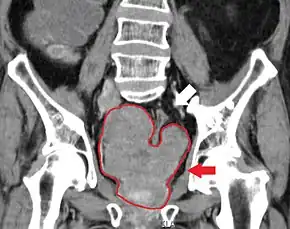

The most important distinction made by any staging system is whether the cancer is confined to the prostate. In the TNM system, clinical T1 and T2 cancers are found only in the prostate, while T3 and T4 cancers have metastasized. Several tests can be used to look for evidence of spread. Medical specialty professional organizations recommend against the use of PET scans, CT scans, or bone scans when a physician stages early prostate cancer with low risk for metastasis.[95] Those tests would be appropriate in cases such as when a CT scan evaluates spread within the pelvis, a bone scan looks for spread to the bones, and endorectal coil magnetic resonance imaging evaluates the prostatic capsule and the seminal vesicles. Bone scans should reveal osteoblastic appearance due to increased bone density in the areas of bone metastasis—the reverse of what is found in many other metastatic cancers.